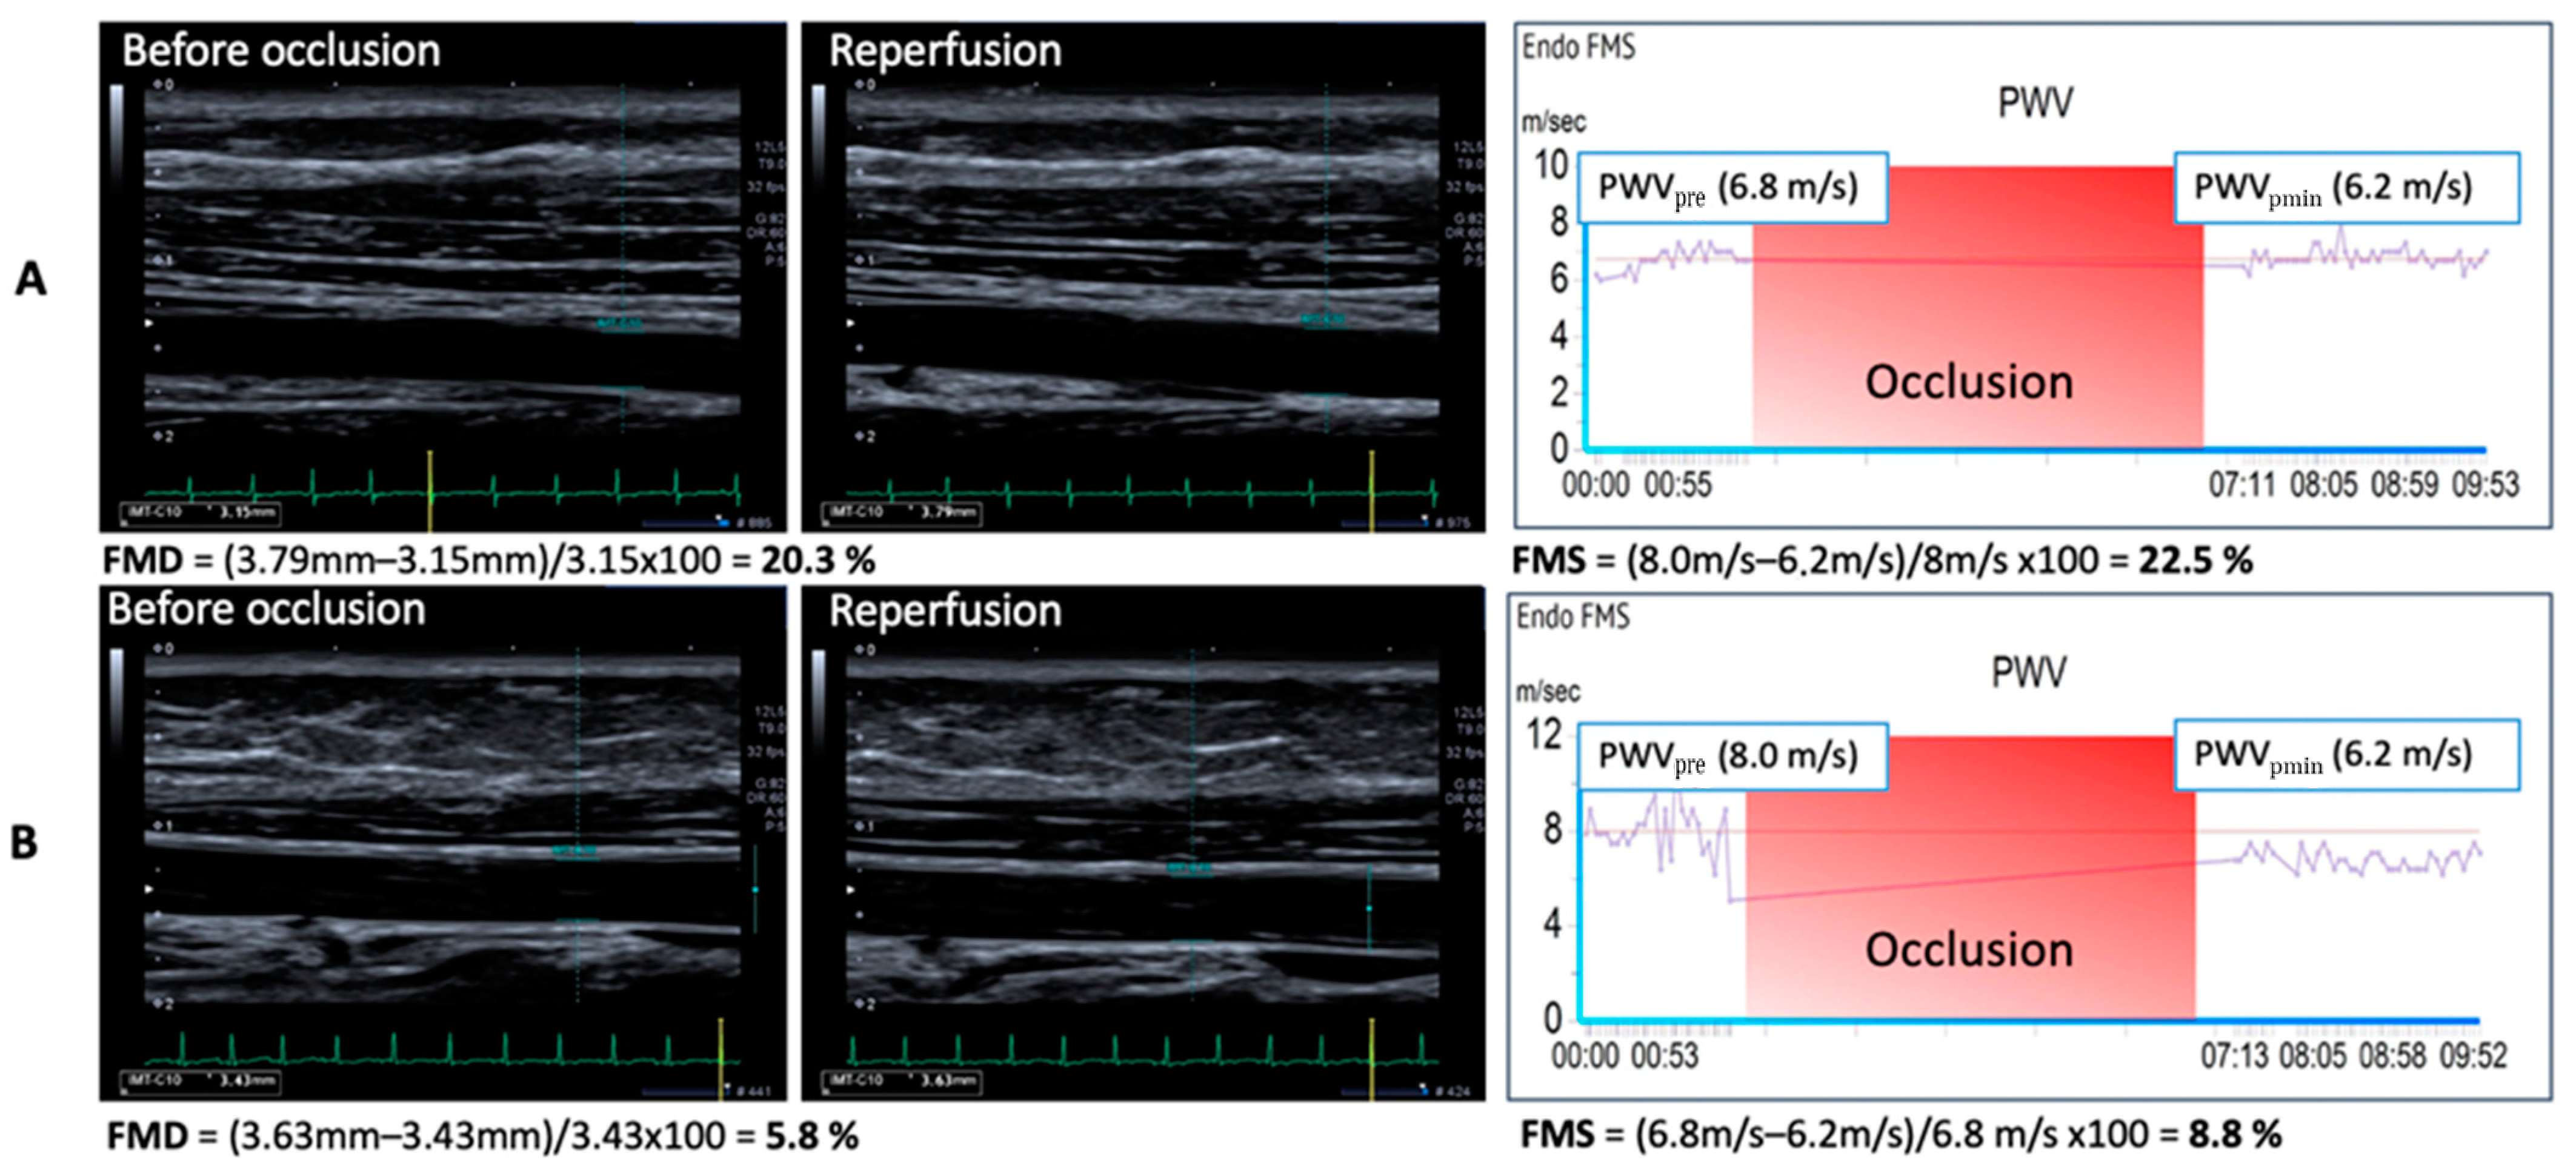

| Patient No | FMD (%) | FMS (%) | Difference % (FMS–FMD) |

| 1 | 10.13 | 15.00 | +4.87 |

| 2 | 10.32 | 15.00 | +4.68 |

| 3 | 3.53 | 8.00 | +4.47 |

| 4 | 15.61 | 18.00 | +2.39 |

| 5 | 4.67 | 8.00 | +3.33 |

| 6 | 21.99 | 24.00 | +2.01 |

| 7 | 8.00 | 10.00 | +2.00 |

| 8 | 12.80 | 17.00 | +4.20 |

| 9 | 17.41 | 22.00 | +4.59 |

| 10 | 2.89 | 2.00 | −0.89 |

| 11 | 2.88 | 7.00 | +4.12 |

| 12 | 9.94 | 7.00 | −2.94 |

| 13 | 15.73 | 17.00 | +1.27 |

| 14 | 2.84 | 4.00 | +1.16 |

| 15 | 16.20 | 16.00 | −0.20 |

| 16 | 18.10 | 14.00 | −4.10 |

| 17 | 13.80 | 15.00 | +1.20 |

| 18 | 9.60 | 10.00 | +0.40 |

| 19 | 10.85 | 15.00 | +4.15 |

| 20 | 13.82 | 19.00 | +5.18 |